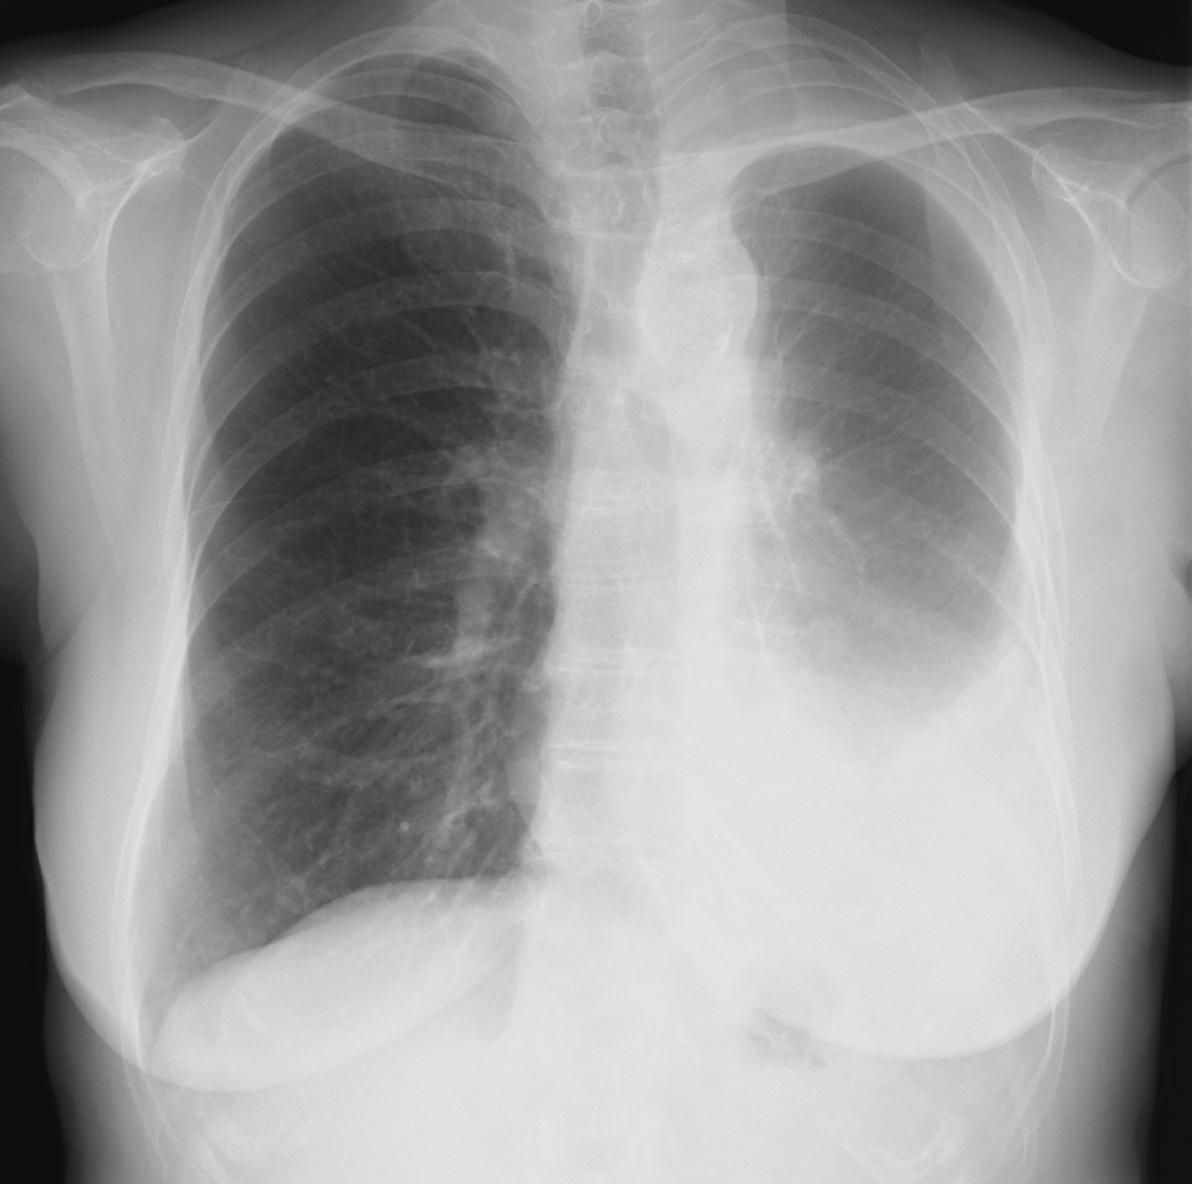

見逃しのないよういつも一定の順序で読む。胸郭→左右肺野の明るさの対比→中央陰影→気管支系→血管系→肺区域の確認→異常所見

ならびに異常陰影の検出と同定→情報をもとにレントゲン診断する→病態と矛盾しないか検討する。

縦隔の拡大があり内部をみると血管陰影もしくは左房陰影の可能性があるが、右縁は大動脈弓に連続しており大動脈の蛇行(上行・胸部)と考えられる(横型心陰影にみられる正常バリエ-ション)右S3の結節影と縦隔の下部の不鮮明な所見には注意。

肺野の含気過多があり細気管支炎様のレントゲン像だが、同時に上縦隔右気管支上の部分が反対側の左と比べてやや白く透過性が悪くなっている。このような場合気管支S1もしくはS2の浸潤影初期のことがある。